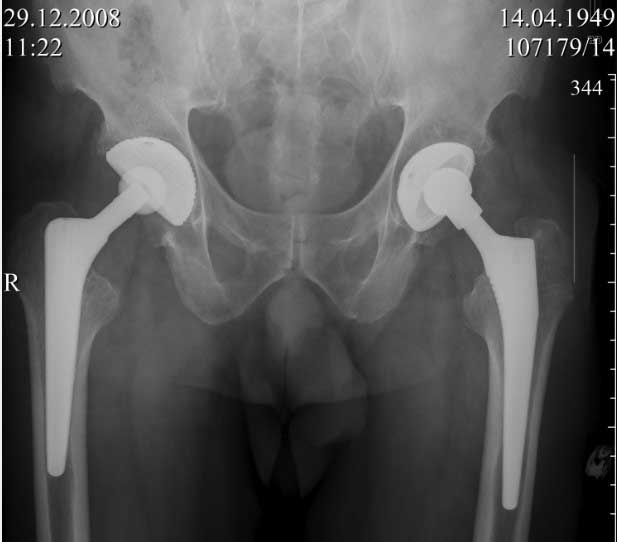

Хочу доложить, недавний случай.

Пациент 60 лет, мужчина. Оперирован в 2007 году, поочередно оперированы два тазобедренных сустава с интервалом в 4 месяца. В 2008 году оперирован на сердце(аорто-коронарное шунтирование).Операция осложнилась инфицированием операционной раны в области грудины, лечился в гнойном отделении.

В конце 2008 года отметил боли в правой паховой области при опоре на правую ногу. На рентген снимках таза с тазобедренными суставами явных признаков нестабильности вертлужного компонента не обнаружено. В 2009 году нейрохирурги его "успешно" прооперировали на L\3-\4 связывая болевой синдром в правой паховой области с наличием грыжи указанного межпозвонкового диска. Состояние только ухудшилось, больной уже не мог долго сидеть, боль прогрессировала . Его в 2009 и 2010 годах смотрел ортопед, делались рентгенснимки, но почему то приходили к выводу что эндопротез справа стабилен. В марте 2011 года я впервые увидел его, через одну неделю после этого был прооперирован. На операции вертлужный компонент при упоре на него инструментом прокручивался во впадине и без труда был извлечен.

ниже снимок в 2008 году